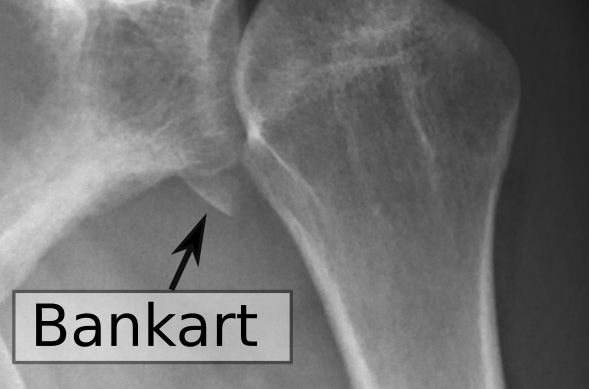

A Bony Bankart lesion is a fracture of the front rim of the shoulder socket (glenoid) usually caused by shoulder dislocation. Unlike soft tissue Bankart injuries, this involves a piece of bone. Recognizing it early and getting expert care from Dr. Kruse can prevent future instability and long-term damage.

– Definition in simple terms: When your upper arm bone (humerus) pops out of the socket (glenoid), it can break a small piece off the socket rim. That fragment is a bony Bankart lesion.

- X-rays may show the bone fragment if it’s big enough.